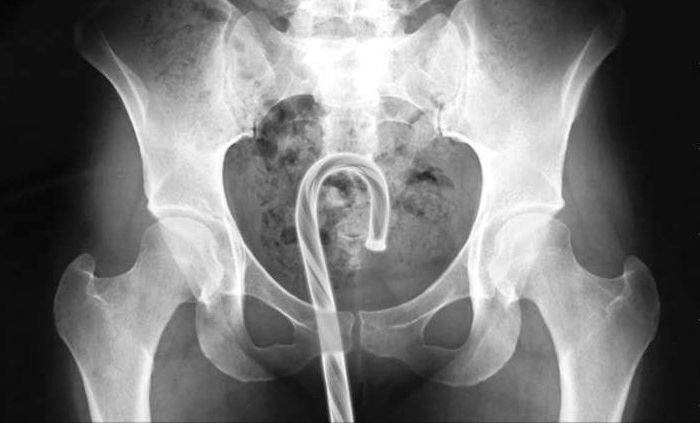

▼這個應該是拐杖糖果而不是雨傘吧

圖片來自:ems1